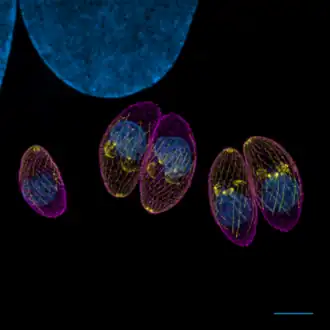

| Toxoplasma gondii (tachyzoïten) | |||||||||||||

Deze kan in elk type cel van de tussengastheer plaatsvinden (de mens, maar ook een grote variëteit aan dieren), behalve in de rode bloedcellen. Het actieve stadium van de parasiet is de tachyzoïet. Deze komt na het inslikken vrij uit de oöcyste of uit de weefselcyste, dringt de gastheercel binnen en deelt intracellulair. Het delingsproces gaat door tot de gastheercel barst. De vrijgekomen tachyzoïeten dringen direct weer nieuwe cellen binnen en beginnen opnieuw met delen. Door een nog niet geheel begrepen mechanisme ontstaat na enige tijd een omslag in dit proces en ontstaan weefselcysten. Deze bevatten bradyzoïeten, dat wil zeggen een veel trager stadium van de parasiet met een zeer laag stofwisselingsniveau en slechts weinig deling. De bradyzoïet bevindt zich in de intracellulaire weefselcyst met een diameter van ongeveer 100 μm en bevat enkele duizenden parasieten. De weefselcysten variëren in grootte (tot 200 μm) en bevatten wisselende aantallen parasieten, variërend van enkele tot 3000 bradyzoïeten.

Tachyzoïten -

Twee tachyzoïten omgeven door een membraan -